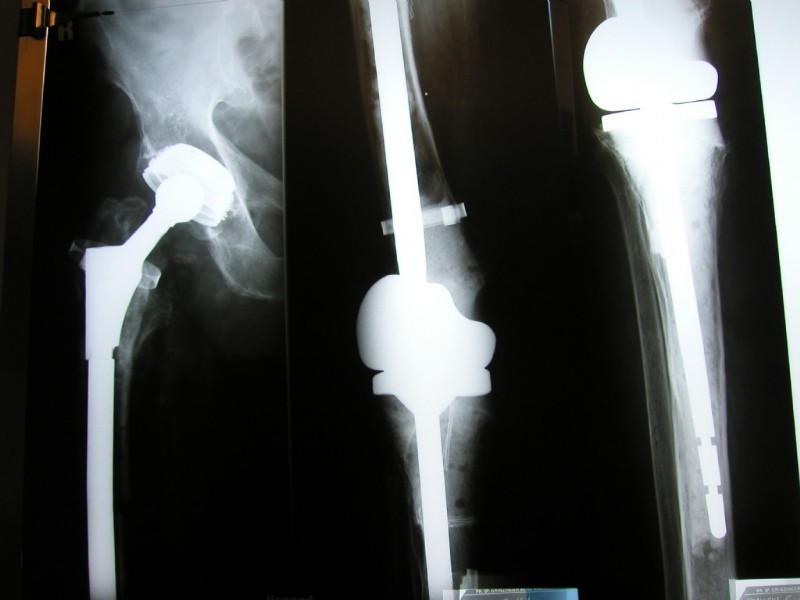

Right: A so-called "total femur": A solution for desperate cases, in which there is no other way to preserve the limb: The hip (left) and knee (center and right) had to be completely replaced in a session. The anchorage is deep into the lower leg. The hip and knee part are strongly connected through the femur. It is a so-called tumor prosthesis.

Example of a complete prosthesis